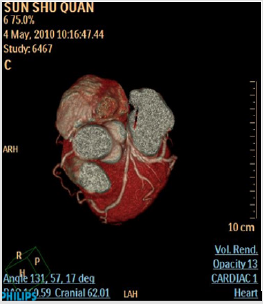

A 67-year-old man presented progressive chest pain after physical exertion for ten months, he was admitted to our hospital on November 6th, 2009. He suffered from diabetic mellitus and hypertension for eight years. Coronary angiogram was performed through trans-radial approach. An angiogram demonstrated a single coronary artery: the LMCA originating from the proximal of right coronary artery and then dividing into the left anterior descending artery (LAD) and the left circumflex artery (LCX). In LAO projection there was borderline lesions at the body of the LMCA, it was about 1.5cm lesions in length. There was mild narrowing in the mid of LAD segment, and the LCX, RCA were patent (Figures 1-3). As the lesions of LMCA are borderline, neither percutaneous coronary intervention (PCI) nor coronary artery bypass graft surgery (CABG) was performed, the patient was treated by oral medications including aspirin, nitroglycerine, atorvastatin and ACEI drugs. He was free of chest pain during a 24- month follow-up. In order to confirm the origin and course of the anomalous LMCA, a 64-slice computed tomography (MSCT) of the heart was performed on a 64-slice machine (Philips 64 Slice, Philips, Netherland) after 6 months of coronary angiography. The results showed the anomalous left main coronary artery originating from the proximal of the RCA, posterior to the aorta then taking an acute bend to course between the aorta and left atrium (Figures 4&5). The anomalous LMCA was classified as R-II P subtype.

Figure 5: Reconstructed three-dimensional image obtained by volume-rendering technique shows the anomalous LMCA coursed between the aorta and left atrium.

The case we presented is the anomalous LMCA arising from the proximal of right coronary artery (RCA). The origin and course of anomalous LMCA was confirmed by MSCT technique [7], the results demonstrated that the anomalous LMCA coursed between the aorta and left atrium. The anomalous LMCA was classified as R-II P subtype (retroaotic course). We bring forth the case in an attempt to highlight their significance. The anomaly is considered to be an independent risk factor for adverse cardiovascular events including sudden cardiac death and dealing with their lesions is a challenge to cardiologists. Coronary anomalies are usually detected during coronary angiography. However, X-ray angiography is limited by its inability to provide information regarding the spatial orientation of the anomalous artery with regarding to the surrounding cardiovascular structures [4,5]. With the help of science and technology, MSCT technique has the potential to accurately visualize the coronary artery [7] and clearly demonstrate the surrounding cardiovascular structures of the anomalous coronary artery [8].

In the present case, the MSCT images clearly demonstrated the origin and course of the anomalous left main coronary artery. It was belonged to R-II P subtype (retroaotic course). So we bring forth the case in an attempt to highlight their significance, and make cardiologist understood what important the anomalies are. A single coronary artery provides a unique challenge to cardiologists when dealing with critical lesions of coronary vasculature, which would otherwise have been easily amenable to angioplasty. Presence of coronary artery anomalies create challenges during coronary angiography, Percutaneous coronary interventions, and coronary artery bypass graft surgery [9]. It is very important to interventional cardiologist and cardiac surgeon in clinical practices [10].